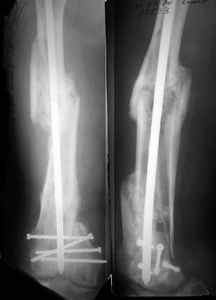

Attached are few examples from our Hospital:

B. Fixation loosening: distal cutting of the nail, non-unions do happen (cases attached).

Locking Plating has more distal screws than any nail, fixed angles and provides much better fixation, especially in osteoporotic bone.